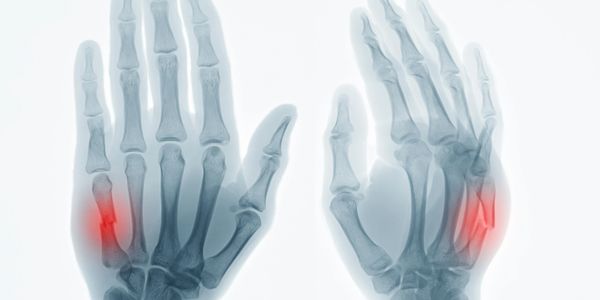

También damos manejo a secuelas de trauma de la mano y muñeca tales como uniones patológicas, artrosis, inestabilidad del carpo, inestabilidad del fibrocartílago triangular.

Contamos con un amplio portafolio de tratamientos quirúrgicos para la mano artrítica como para los problemas degenerativos no reumáticos de las articulaciones. Entre ellos la osteoartritis, artrosis de la base del pulgar, etc.